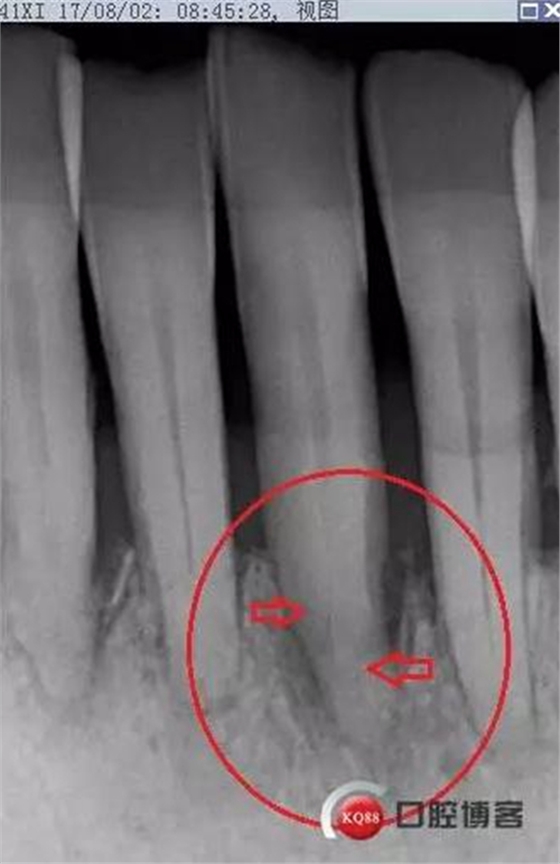

X線示牙槽骨吸收,下頜前牙區(qū)可見齦下牙石影像,牙槽骨吸收至根尖1/3,根周透射影像。

X線示根周透射影骨密度增高。

事后再次查看術(shù)前片,可以看到兩個(gè)根管影像,忽略了。